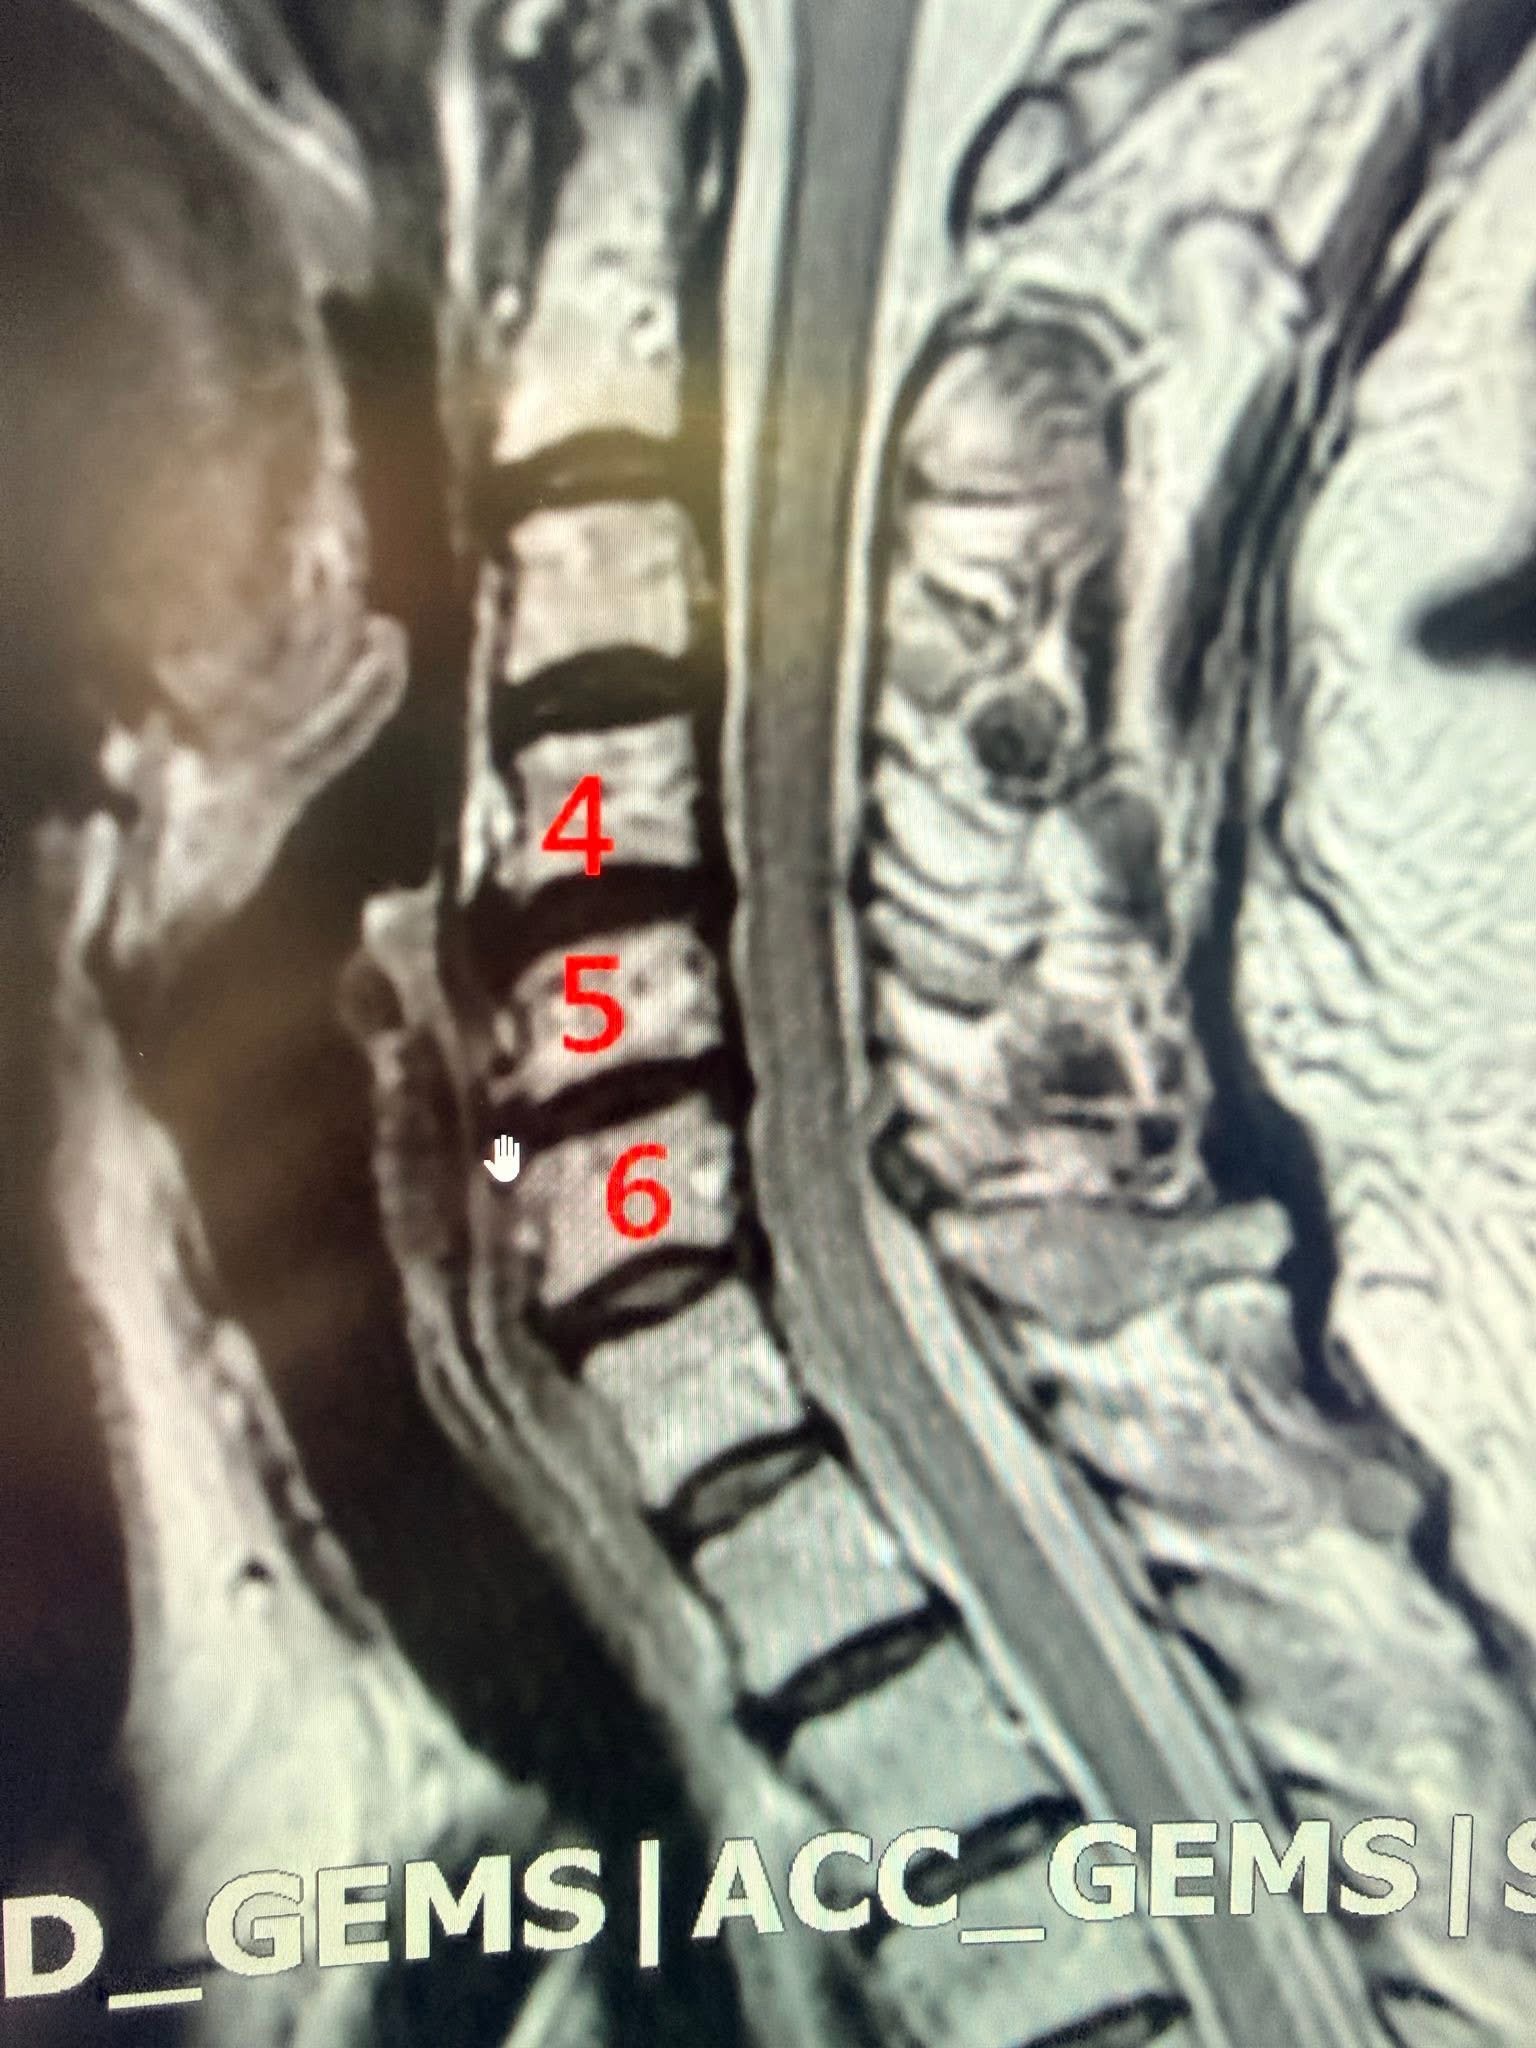

黃阿姨,長年旅居美國,卻因頸椎椎間盤突出而苦不堪言。持續的肩痛與手麻,讓她連夜晚睡眠都變得破碎。MRI 影像顯示,C4/5、C5/6 椎間盤突出,壓迫神經根,正是造成症狀的元兇。

(註:本文所有費用對比與治療效果,均基於臨床經驗,具體療程與費用仍需經由專業醫師評估。圖片所示為患者 C4-C6 節段的 MRI 影像)